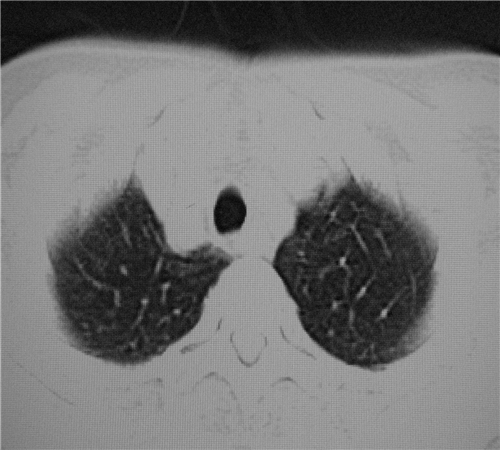

标题: CT26849:女67岁反复胸痛两天余,临床考虑夹层。 [打印本页]

标题: CT26849:女67岁反复胸痛两天余,临床考虑夹层。

双下肺感染,右侧显著。有无夹层,增强扫描后再诊断。

1. 感染性病变,2.未见夹层,3.食道未见异常。

1.考虑双肺感染,右侧为重;2.建议ct增强或mri排除主动脉夹层